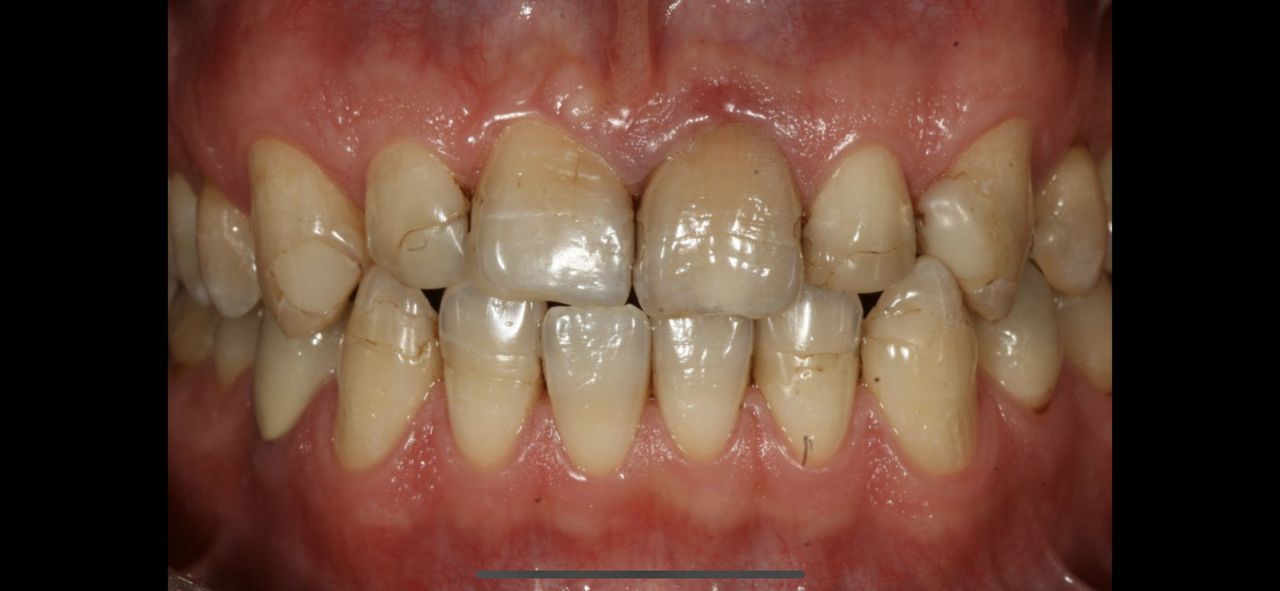

Zdjęcia i filmy

Pan dok.Polakowski to profesjonalista, tam gdzie nikt nie chciał zająć się moimi zębami

P.dok wyczarowal piękny uśmiech.

• Duo-Dent odbudowa zębów  •